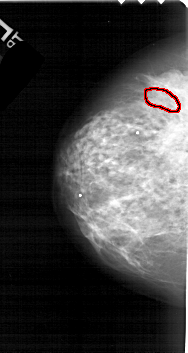

A_1766_1.LEFT_CC

FILE: A_1766_1.LEFT_CC.OVERLAY

TOTAL_ABNORMALITIES 1

ABNORMALITY 1

LESION_TYPE CALCIFICATION TYPE AMORPHOUS DISTRIBUTION CLUSTERED

ASSESSMENT 4

SUBTLETY 1

PATHOLOGY MALIGNANT

TOTAL_OUTLINES 1

BOUNDARY